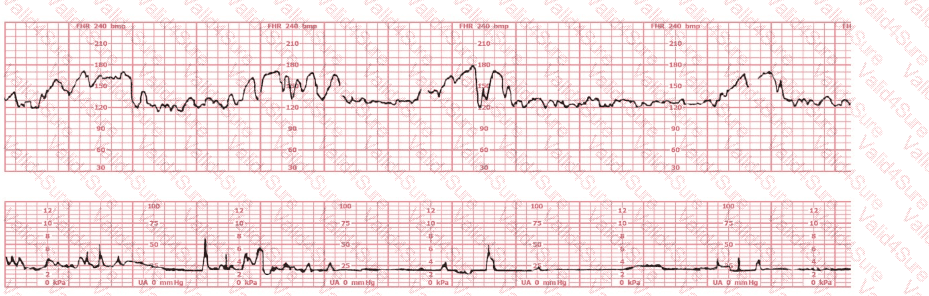

A woman at 39-weeks gestation is in early labor, 2–3 cm dilated, 85% effaced, and –2 station. Based on the fetal heart rate tracing shown, what is the most appropriate first intervention?